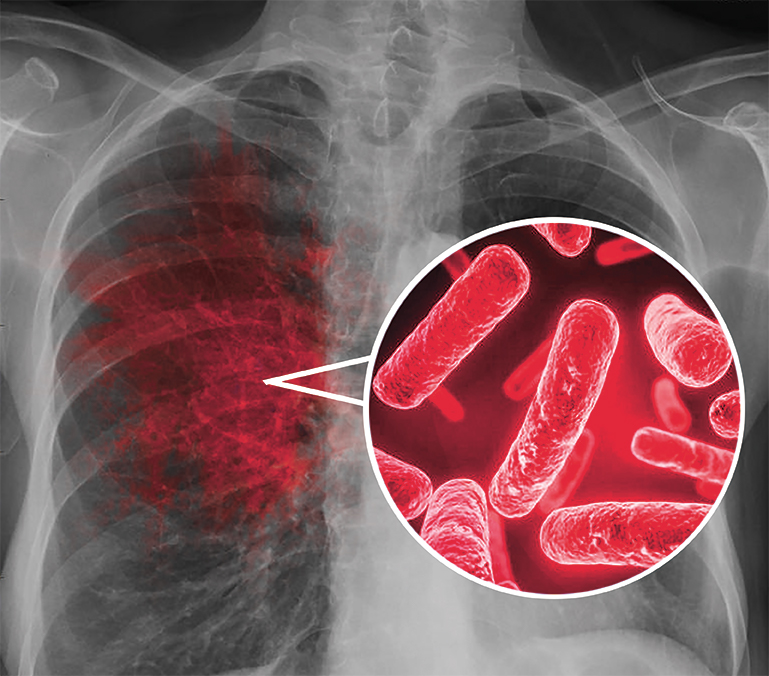

Симптомы туберкулеза: Как распознать и что делать

Раздел: Визуальные уроки